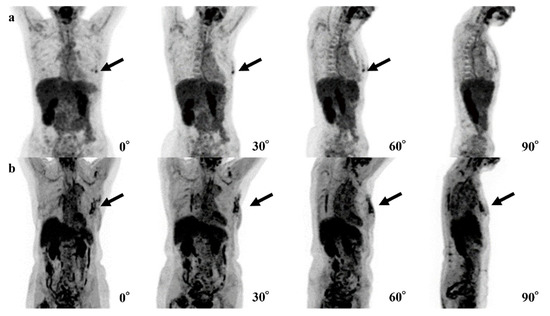

| Case | Age | SUVmax | Breast Density | Size of Invasive Components (mm) | Total Tumor Size (mm) | Pathology and Subtype | ER | PgR | HER2 | Ki67 |

|---|---|---|---|---|---|---|---|---|---|---|

| 1 | 44 | 2.0 | Heterogeneously | 11 | 11 | IDC | + | + | - | 9.1% |

| 2 | 70 | 0.9 | Scattered | None | 0.6 | DCIS | + | - | + | 15.4% |

| 3 | 70 | 1.2 | Heterogeneously | None | 8 | DCIS | + | + | + | 12.0% |